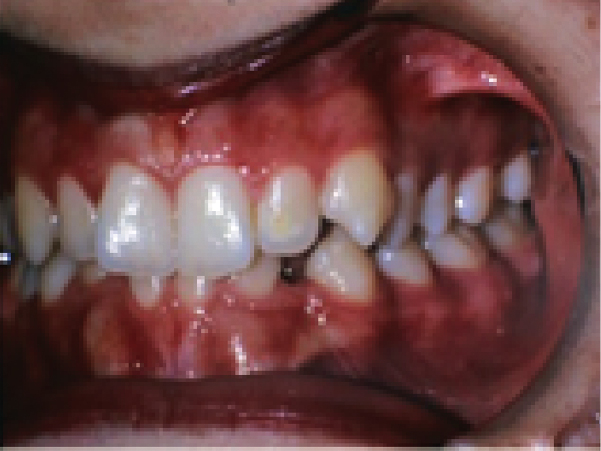

- Opis przypadku: Dziewczynka w wieku 13 lat i 9 miesięcy zgłosiła się do kliniki ortodontycznej, uskarżając się na nadmierne rozstawienie i brak zębów w uzębieniu żuchwy.

Streszczenie: Zatrzymane i przemieszczone zęby poważnie zakłócają wyrzynanie się i fizjologiczny ruch sąsiadujących z nimi zębów, będąc przyczyną zaburzeń estetycznych i funkcjonalnych. Właściwe planowanie leczenia, w tym odpowiedniej kontroli biomechanicznej, ma zasadnicze znaczenie dla uniknięcia efektów ubocznych w okresie trakcji i wyrównywania położenia zębów zatrzymanych i/lub przemieszczonych. Celem niniejszej pracy było przedstawienie pacjentki z zatrzymanymi i przemieszczonymi kłami, skutecznie leczonej z zastosowaniem zmodyfikowanego łuku językowego i stałego aparatu ortodontycznego. Dziewczynka w wieku 13 lat i 9 miesięcy zgłosiła się do kliniki ortodontycznej, uskarżając się na nadmierne rozstawienie i brak zębów w uzębieniu żuchwy. Po wyrównaniu zębów żuchwy i stworzeniu wystarczającej przestrzeni dla kłów do pierwszych trzonowców żuchwy przytwierdzono zmodyfikowany łuk językowy. Łuk językowy posiadał dwa haczyki sięgające do dystalno-policzkowych granic przestrzeni na kły. Pomiędzy tymi haczykami a zaczepami przytwierdzonymi do koron kłów rozciągnięto wyciągi elastyczne. Niewielkie siły generowane przez materiały elastyczne spowodowały wyrznięcie się zatrzymanych kłów i przesuwanie się ich w kierunku odpowiednich przestrzeni w łuku zębowym. Ostatecznie zatrzymane i przemieszczone kły zostały prawidłowo ustawione [...]